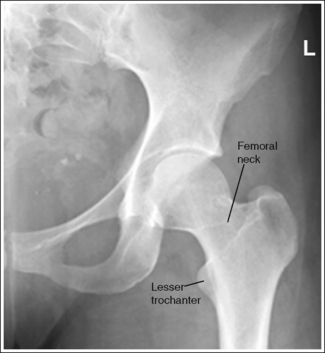

The pelvis demonstrates an AP projection. The ischial spine is aligned with the pelvic brim, the sacrum and coccyx are aligned with the symphysis pubis, and the obturator foramen is open.

• An AP projection of the hip is obtained by placing the patient supine on the imaging table with the legs extended (Figure 7-3). To ensure that the pelvis is not rotated, judge the distances from the anterior superior iliac spines (ASISs) to the imaging table. The distances on each side should be equal.

• Detecting pelvis rotation. Rotation on an AP hip projection is initially detected by evaluating the relationship of the ischial spine and the pelvic brim, the alignment of the sacrum and coccyx with the symphysis pubis, and the degree of obturator foramen demonstration. If the patient was rotated toward the affected hip, the ischial spine is demonstrated without pelvic brim superimposition, the sacrum and coccyx are not aligned with the symphysis pubis but are rotated away from the affected hip, and the obturator foramen is narrowed (see Image 1). If the patient has been rotated away from the affected hip, the ischial spine is not aligned with the pelvic brim but is demonstrated closer to the acetabulum, the sacrum and coccyx are not aligned with the symphysis pubis, but are rotated toward the affected hip, and the obturator foramen is widened (see Image 2).